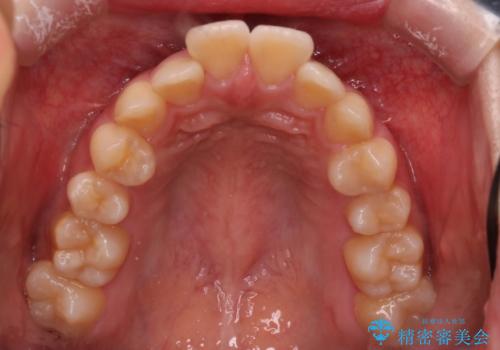

【インビザライン】アンカースクリューを用いた遠心移動

- 前歯の突出を主訴に来院されました。

アンカースクリューとインビザラインを用いて遠心移動を行うことでできる限り前歯を下げて叢生の改善を行いました。